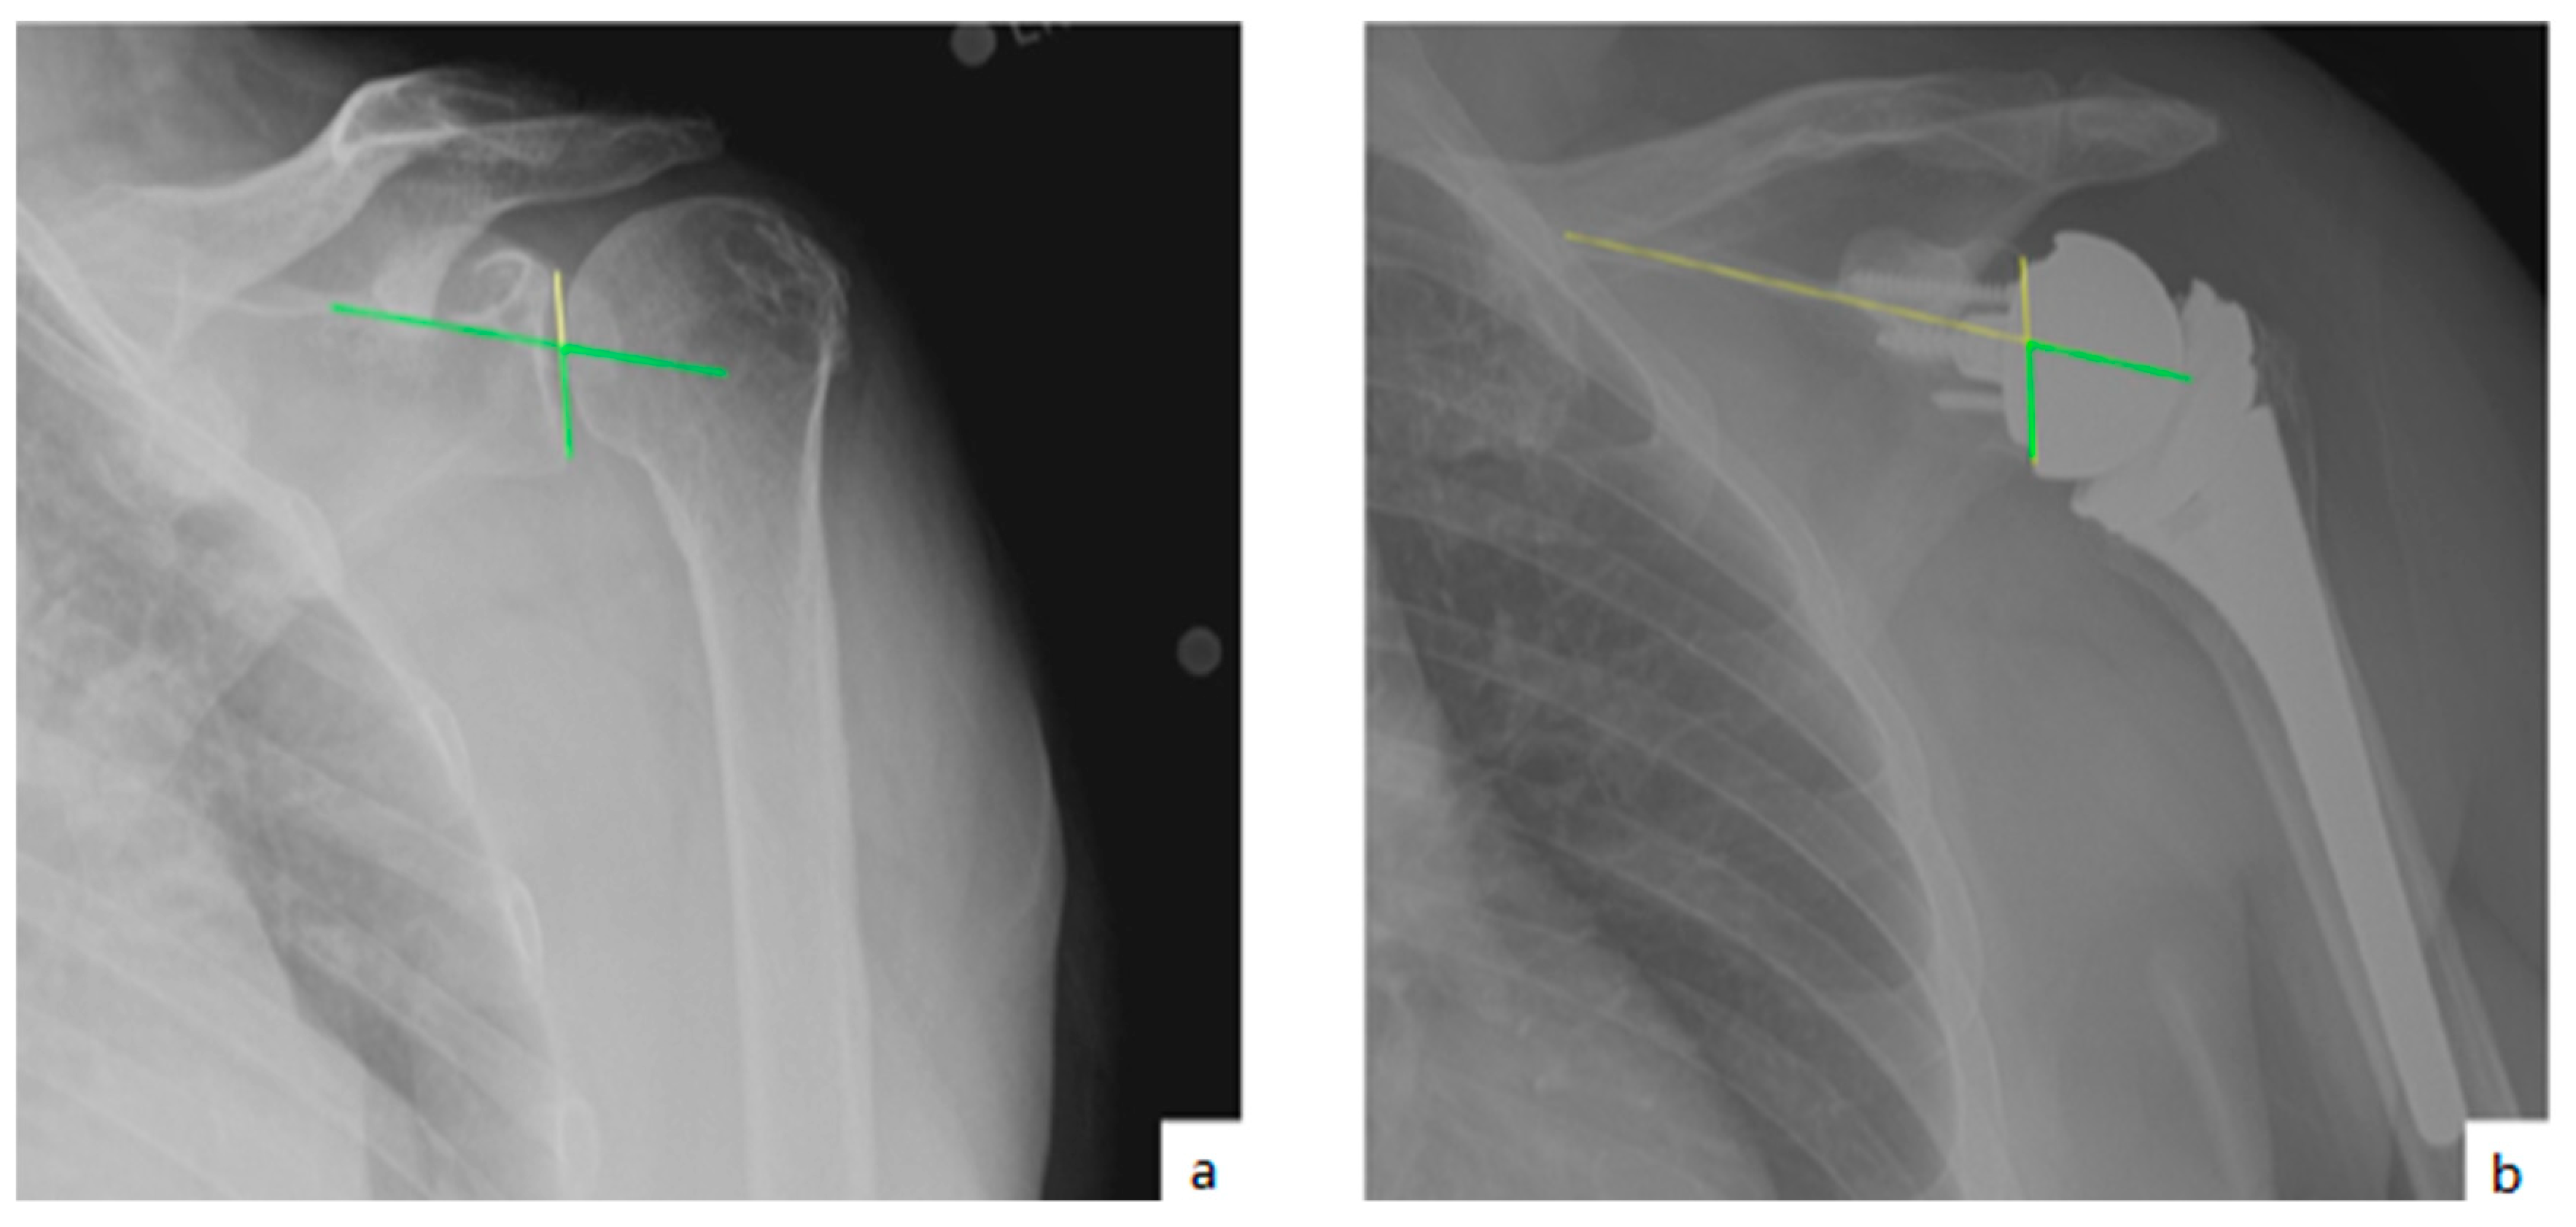

AHD was measured by calculating the perpendicular distance between the most lateral portion of the undersurface of the acromion and a line parallel to the superior border of the greater tuberosity [21] (Figure 1). LHO was measured by determining the distance from the AHD line to the most lateral projection of the greater tuberosity [21] (Figure 2). LSA was measured by drawing a line from the superior glenoid tubercle to the most lateral border of the acromion and a second line from the most lateral border of the acromion to the most lateral border of the greater tuberosity. The angle between these two lines formed the LSA [20] (Figure 3a). DSA was measured by drawing a line between the most lateral border of the acromion and the superior glenoid tubercle and drawing a second line to connect the superior glenoid tubercle with the most superior border of the greater tuberosity. The angle between these two lines formed the DSA [20] (Figure 3b). Glenoid and baseplate were determined as the angle between the floor of the supraspinatus fossa and the glenoid fossa [25] (Figure 4). COR was measured by determining the best fit circle flush to the articular surface, identifying the center of the circle in the humeral head, and then measuring the distance of the perpendicular line between the center of the humeral head and the midpoint of the line connecting the superior and inferior glenoid tubercles [24] (Figure 5b). CSA was measured by a line from the superior pole to the inferior pole of the glenoid and a line from the inferior pole to the lateral edge of the acromion [26] (Figure 5a). In addition, scapular notching was graded according to the Nerot–Sirveaux classification and severity of preoperative cuff tear arthropathy was evaluated according to the Hamada classification [27,28].

Figure 4.

(a) Glenoid inclination (green angle); (b) baseplate inclination (green line).